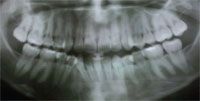

Which Ones to Remove?

Case Number: 161198

Here is a Hispanic female in her 30s with a straight profile, minimum overjet, midline shift and blocked out lower right canine. What lower teeth would you recommend to extract?